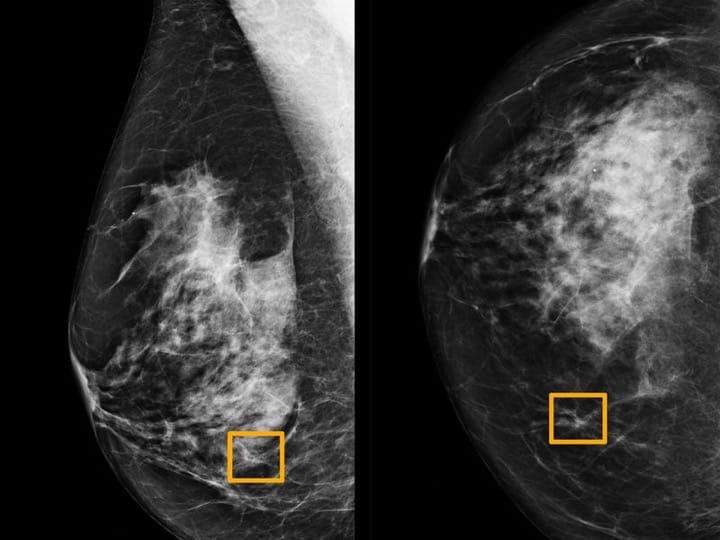

یک توده سرطان سینه ممکن است احساس گرد، نرم و لطیف داشته باشد و میتواند در هر نقطهای از سینه ایجاد شود.معاینات فردی تا تشخیص سرطان سینهآخرین دستورالعملهای انجمن سرطان آمریکا (ACS) نشان میدهد که معاینات فردی، مخصوصاً برای زنانی که ماموگرافی غربالگری را انجام میدهند، و یا حتی وقتی پزشکان این آزمایشات را انجام میدهند فواید، آشکاری حاصل نشده است، هنوز هم برخی از مردان و زنان وجود دارند که به سرطان سینه مبتلا میشوند و علائم آن را در خود مییابند.اگر زن هستید، مهم است که با ظاهر سینه خود آشنا شوید و آنها را مرتباً بررسی کنید. این کار به شما کمک میکند تا از هرگونه تغییر یا ناهنجاری در هنگام وقوع آگاه شوید. زنان برای سلامتی خود باید چکاپ روتین داشته باشند که معاینه منظم سینهها از مهمترین موارد آن است.یک توده سرطان سینه چه حسی دارد؟موارد توده سرطان سینه، احساس یکسانی ندارند. پزشک شما باید هر نوع تودهای را بررسی کند، خواه با رایجترین علائم ذکر شده در زیر مطابقت داشته باشد یا نداشته باشد.معمولاً یک توده سرطان سینه:یک توده سخت استبدون درد استدارای لبههای نامنظم استبیحرکت است (هنگام هل دادن حرکت نمیکند)در قسمت فوقانی پستان شما ظاهر میشودبا گذشت زمان رشد میکندهمه موارد توده سرطان سینه از این معیارها برخوردار نیستند و توده سرطان سینه که همه این صفات را داشته باشد، توده عادی نیست. یک توده سرطان سینه ممکن است احساس گرد، نرم و لطیف داشته باشد و میتواند در هر نقطهای از سینه ایجاد شود. در بعضی موارد، توده سرطان سینه حتی میتواند دردناک نیز باشد.برخی از خانمها همچنین بافت متراکم و الیافی پستان دارند. که در این صورت، احساس توده سرطان سینه یا تغییر در سینه ممکن است دشوارتر باشد.داشتن سینههای متراکم نیز تشخیص سرطان سینه را در ماموگرافی دشوارتر میسازد. با وجود داشتن بافت سختتر، هنوز هم میتوانید به محض وقوع تغییر در پستانها، آن را تشخیص دهید.

داشتن سینههای متراکم نیز تشخیص سرطان سینه را در ماموگرافی دشوارتر میسازد.چه زمانی باید به دکتر زنان مراجعه کنم؟سرطان سینه شایعترین منبع ابتلا به سرطان در زنان در دنیا تشخیص داده شده است. با این حال، بیشتر موارد توده سرطان سینه نیستند. اگر در هنگام معاینه فردی چیزی جدید یا غیرمعمول در سینه خود مشاهده یا احساس کردید، باید به پزشک مراجعه کنید.با وجود آمار و دستورالعملهای ACS، بسیاری از زنان هنوز معاینات فردی را ترجیح میدهند. درباره اینکه معاینات فردی را انجام دهید یا نه، باید با پزشک خود در مورد سن مناسب برای شروع غربالگری ماموگرافی صحبت کنید.پیروی از رهنمودهای غربالگری سرطان سینه، مهمترین کاری است که میتوانید برای اطمینان از تشخیص به موقع سرطان سینه انجام دهید. هرچه سرطان سینه زودتر تشخیص داده شود، درمان زودتر آغاز میشود و چشم انداز بیماری شما بهتر خواهد بود.در زمان ویزیت پزشک چه انتظاری میتوانم داشته باشم؟با دکتر مراقبتهای اولیه یا متخصص زنان خود ملاقات کنید. در مورد ناحیه مشکوک و جدیدی که شناسایی کردهاید و علائمی که احساس میکنید، با پزشک خود صحبت کنید. پزشک شما به احتمال زیاد معاینه کامل سینه را انجام خواهد داد و ممکن است لکههای اطراف را نیز از جمله استخوان چنبر، گردن و زیر بغل شما بررسی کند.پزشک ممکن است بر اساس آنچه احساس میکند، آزمایشهای اضافی مانند ماموگرافی، سونوگرافی یا بافتبرداری را تجویز کند.پزشک شما همچنین ممکن است یک دوره انتظار همراه با مراقب را پیشنهاد کند. در طول این مدت، شما و پزشک به بررسی میزان توده تغییر یا رشد میپردازید. در صورت رشد توده، پزشک باید آزمایشات خود را برای رد توده سرطان سینه آغاز کند.در مورد نگرانیهای خود با پزشک خود صادق باشید. اگر سابقه شخصی یا خانوادگی، شما را در معرض خطر بیشتری برای ابتلا به سرطان سینه قرار میدهد، ممکن است بخواهید آزمایشهای تشخیصی مناسبی را انجام دهید تا مطمئن شوید توده سینه شما توده سرطان سینه است یا خیر.

توده سرطان سینه بیحرکت است. این توده اغلب منجر به سرطان سینه میشود.وزن. اضافه وزن یا چاقی خطر ابتلا به سرطان پستان را افزایش میدهد.بیماری خوش خیم پستان. برخی از بیماریهای خوش خیم (غیر سرطانی) پستان ممکن است خطر ابتلا به سرطان پستان را در آینده تحت تأثیر قرار دهد.استفاده از هورمون. اگر از درمان جایگزینی هورمون (HRT) استفاده کرده باشید یا در حال حاضر از آن استفاده میکنید، احتمال ابتلا به سرطان پستان بیشتر است.سابقه قاعدگی. دوره قاعدگی زودرس (قبل از ۱۲ سالگی) ممکن است خطر ابتلا به سرطان پستان را افزایش دهد.اواخر سن یائسگی. تاخیر در یائسگی (بعد از ۵۵ سالگی) ممکن است شما را در معرض هورمونهای بیشتری قرار دهد، که میتواند ریسک ابتلای شما را افزایش دهد.بافت متراکم سینه. مطالعات نشان میدهد زنانی که بافت پستان متراکمی دارند، احتمال ابتلا به سرطان در آنها بیشتر است. این بافت ممکن است تشخیص سرطان را نیز دشوارتر سازد.سبک زندگی کم تحرک. زنانی که به طور منظم ورزش نمیکنند، بیشتر از زنانی که اغلب اوقات ورزش میکنند دچار سرطان پستان میشوند.مصرف دخانیات. سیگار کشیدن خطر ابتلا به سرطان پستان را به ویژه در زنان جوان که هنوز یائسه نشدهاند، افزایش میدهد.مصرف الکل. به ازای هر نوشیدنی الکلی که مصرف میکنید، خطر ابتلا به سرطان پستان افزایش مییابد. تحقیقات نشان میدهد که نوشیدن مقداری الکل مشکلی ندارد، اما استفاده زیاد از الکل با خطر بالاتر سرطان پستان در ارتباط است.